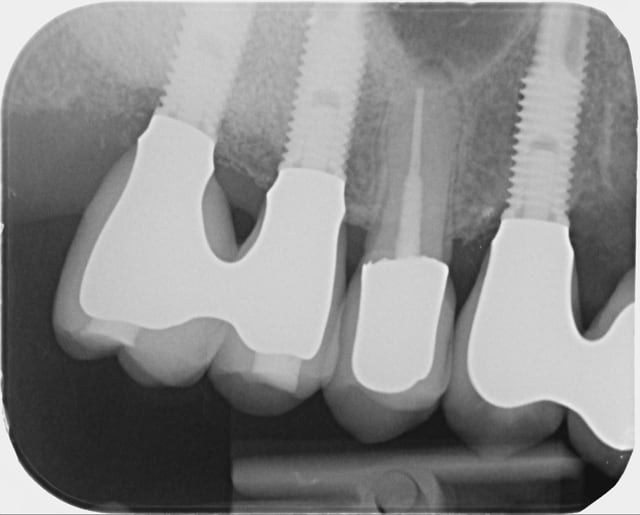

Les 2 premières radios datent de 2009, la dernière d'hier.

Voici la radio lors de la pose.